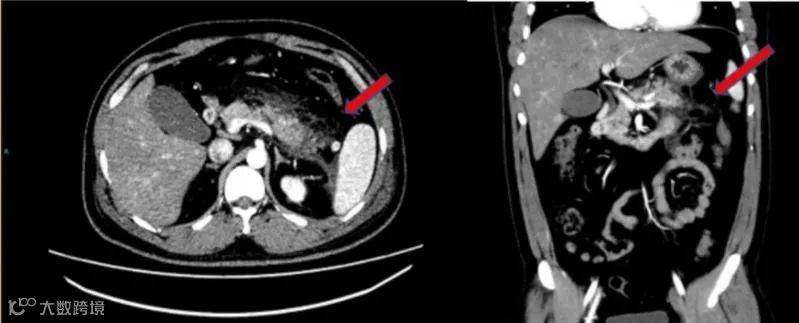

腹部增强CT提示胰腺尾部肿胀,胰腺周围脂肪间隙模糊,多发斑片状、条索影。红色箭头示胰腺脂肪间隙。